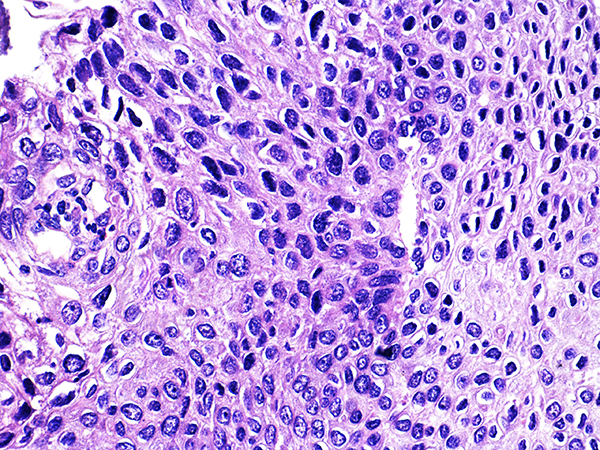

![]() Case 2

Soft Bx CIN 2 10x - Low Power |